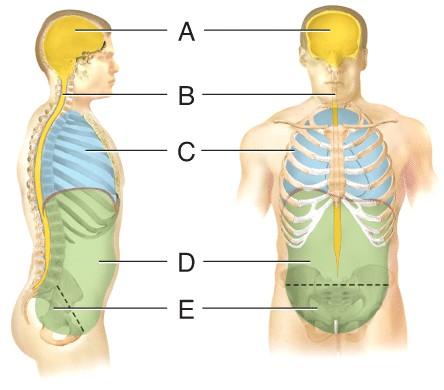

Name the cavity A.

dorsal

cranial

vertebral

ventral

cranial

Name the cavity C.

cranial

thoracic

abdominal

pelvic

thoracic

Name the cavity formed by A and B.

abdominopelvic

ventral

dorsal

pelvic

dorsal

Name the cavity formed by D and E.

ventral

abdominopelvic

dorsal

thoracic

abdominopelvic

Name the cavity formed by C, D and E.

dorsal

cranial

ventral

abdominopelvic

ventral

Name the cavity E.

cranial

pelvic

abdominal

thoracic

pelvic